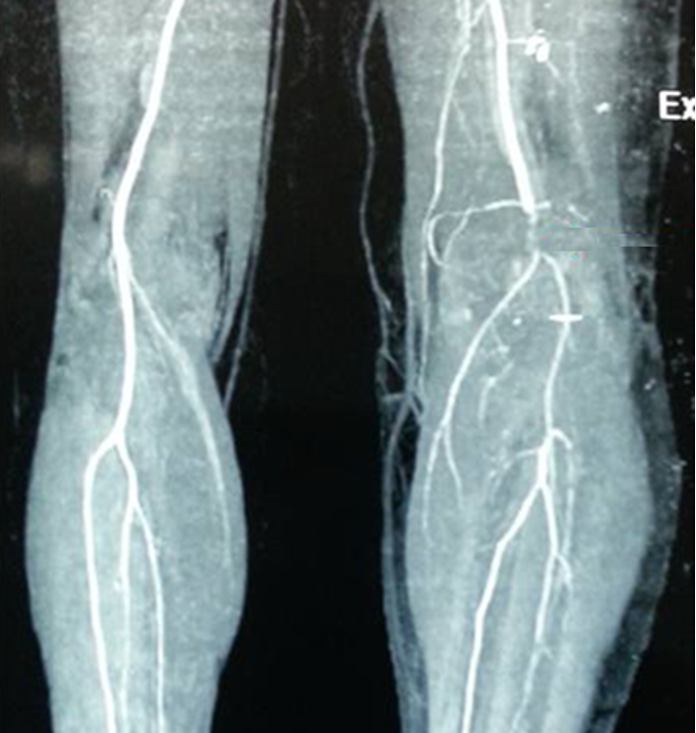

CT angiogram

Normal CT angiogram Popliteal artery stenosis following knee dislocation

Popliteal artery transection following left knee dislocation

Advantages

- readily available, non invasive

- extremely accurate

- also used confirm the site and mechanism of injury

- multi-detector CT

- 100% sensitive and specific in detecting clinically significant arterial injury

Gakhal et al. Vascular and Interventional Radiology 2009

- CTA signs of lower extremity vascular trauma